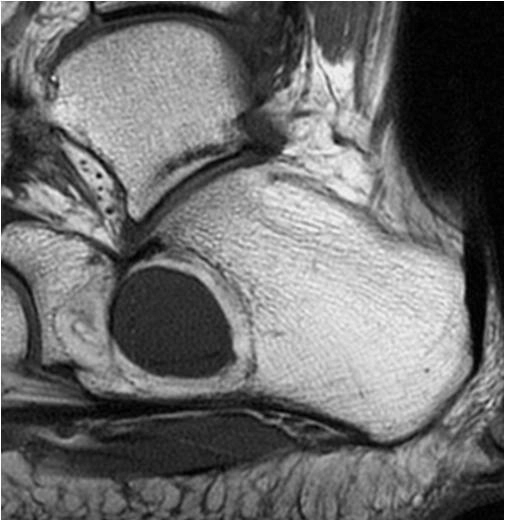

U giả do Hemophilia (Hemophilic pseudotumor)